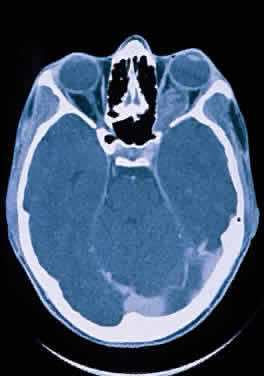

Fig. 14. Computed tomographic scan of head, showing hypoplastic left optic nerve.

Hypoplasia of the optic nerve is also rare but is more common than aplasia (Figs. 13 and 14). It represents one of the most important developmental abnormalities of the eye and is increasingly recognized as a significant cause of visual deficit in children. Congenital nerve hypoplasia is a nonprogressive condition associated with a reduction in the number of retinal ganglion cells and axons. It may be either unilateral or more commonly bilateral and may involve the entire nerve or be segmental. Although a hypoplastic optic nerve is usually idiopathic, an increased incidence has been noted in the offspring of diabetic mothers and with the maternal use of phenytoin, quinine and, alcohol. Rare reports of an inherited disorder may be found in the literature. Although it may be an isolated abnormality, the hypoplasia is frequently associated with other anomalies—both ocular and nonocular. Additional ocular abnormalities include microphthalmos and congenital nonattachment of the retina. The most common nonocular abnormalities associated with congenital optic nerve hypoplasia include midline CNS structural defects, including septo-optic dysplasia of the septum and ectropia of the posterior pituitary, producing diabetes insipidus.

In optic nerve hypoplasia, the optic disc appears gray and is about half its normal size but retinal vessels are present because the optic stalk is invaginated by mesoderm. The optic foramen is also small. Clinically, there may be strabismus, nystagmus, and decreased visual acuity. Severe cerebral abnormalities may be present but the hypoplastic nerve may be the sole abnormality.